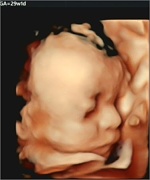

従来の4D画像

当クリニックの4D画像(Voluson S8)

※ 掲載している画像は、「妊娠20週〜37週の胎児4D画像からの一例(当クリニックでの実際の症例)」です。